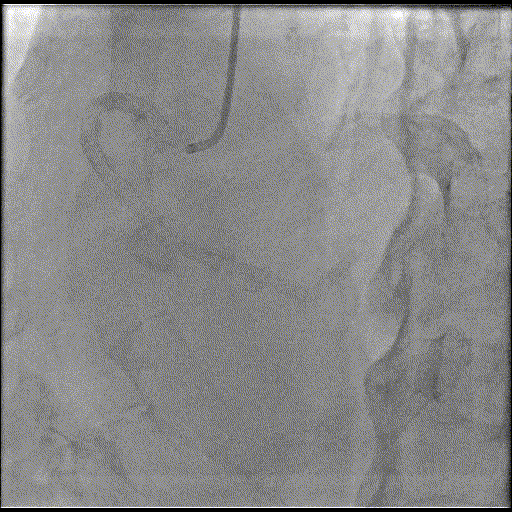

基础造影

右冠状动脉近段原有支架通畅,右冠一后降支细小,开口次全闭塞;左主干狭窄20%;前降支弥漫性病变,近段于间隔支形成分叉病交,最窄可见90%左右狭窄;回旋支近段70%,远段弥漫性病变,最重95%,远段可见侧枝向PDA远段供血。

手术过程

导丝到位

当指引导管冠脉开口到位后,选择三根对应导丝分别送入LCX、OM1、OM2远端。

OM2优先处理:

球囊预扩

当导丝通过病变后其他器械无法通过病变,此时选择不同尺寸的小球囊逐级预扩张病变,复查造影狭窄减轻不明显。为了解血管真实情况,遂启用IVUS检查。

术前腔内影像学IVUS指导

IVUS提示血管可见钙化明显,为360°环形钙化。遂考虑启动IVL治疗。

冲击波球囊治疗

2.5*12mm@4atm 冠脉血管内冲击波导管反复进行4个周期治疗,复查造影提示狭窄减轻。

支架植入并后扩

于OM2-LCX远端植入一枚药物洗脱支架,经非顺应性球囊后扩张支架,复查造影提示支架贴壁良好,未见夹层、血肿。

OM1处理:

使用预扩球囊处理OM1病变。

于OM1病变处植入一枚药物洗脱支架,经非顺应性球囊后扩张支架,复查造影提示支架贴壁良好,未见夹层、血肿。

最终,于LCX中远段行FFR检测,结果为0.78。鉴于本次手术时间较长、造影剂用量饱和,且患者症状已有效缓解、血流状态稳定。经综合评估后,决定对残余病变实施择期处理。